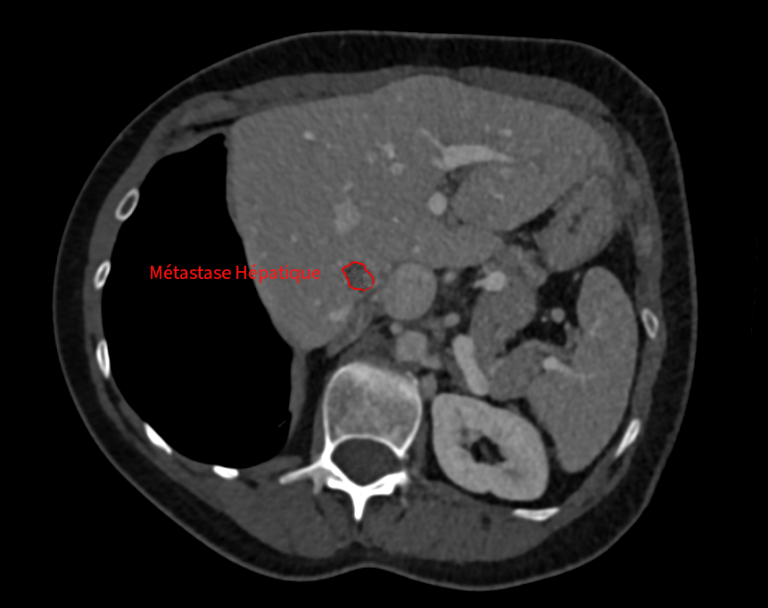

• une métastase hépatique de 1 cm, profonde et difficilement accessible chirurgicalement.

Traitement hépatique par micro-ondes

Dans un second temps, la métastase hépatique est traitée par thermoablation micro-ondes, avec protection des organes voisins grâce à une technique d’hydrodissection.

En images

Images du traitement des organes (poumon et foie) avant, pendant et après le traitement.